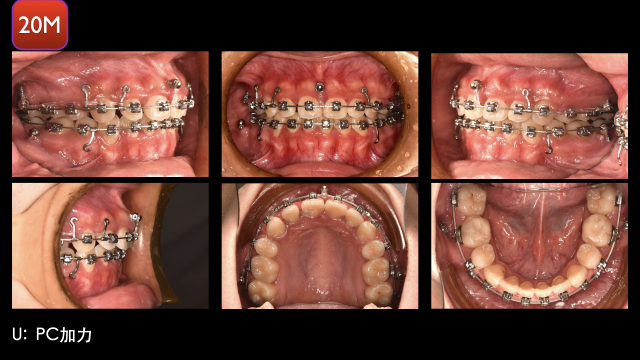

术中治疗